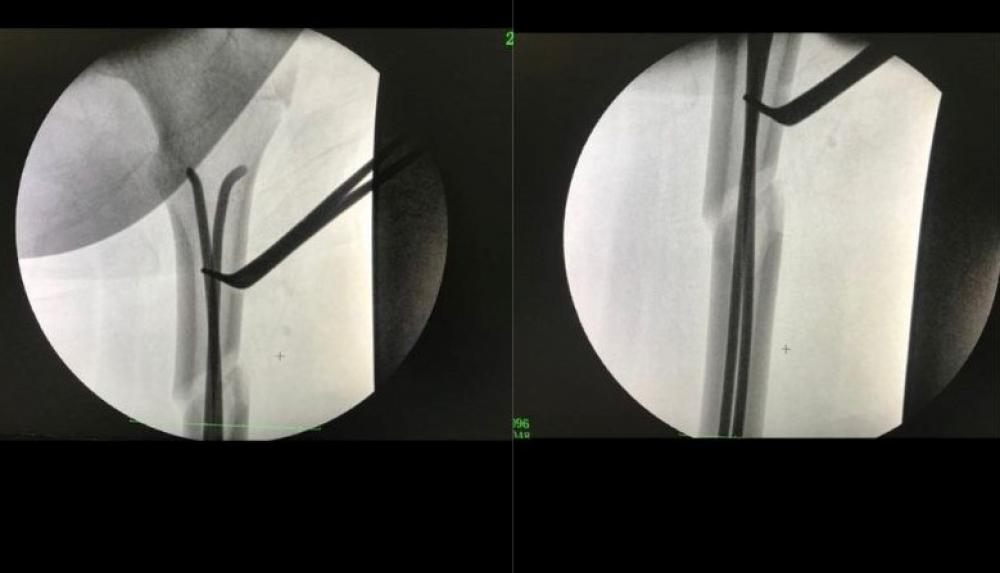

“Одинадцятирічна дитина після ДТП була госпіталізована із закритим перелом правої стегнової кістки у верхній третині зі зміщенням уламків. Пацієнтці проведено малоінвазивне втручання з фіксацією даного перелому двома титановими еластичними стрижнями. Це золотий стандарт лікування переломів довгих трубчастих кісток у дітей у всьому світі. Під час операції здійснюється невеликий розріз шкіри не більше 1.5 см, у середину кістки вводиться титановий стрижень”, - розповів завідувач центру дитячий Ігор Яковець

Це все робиться під контролем електронно-оптичного перетворювача (ЕОП) - сучасного прилада, що допомагає лікарям під час операції відразу бачити точність своєї роботи.